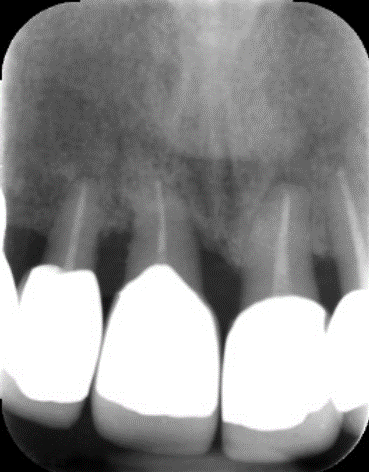

更に、当院では根管治療の精度をさらに高めるために、「CT」も利用しています。CTは一般的な2次元レントゲンと比較し立体的で詳細な画像を撮影できるため、治療必要箇所を見落とすことなく、より高い成功率を実現できます。

上記の画像は、「左」が3次元のCT画像で、「右」が2次元レントゲン画像です。左の赤丸がついている「黒い部分」が問題の箇所ですが、右の画像では黒く映っていません。CTであれば、はっきり確認できるため、治療すべき部位を見落とすリスクが下がります。